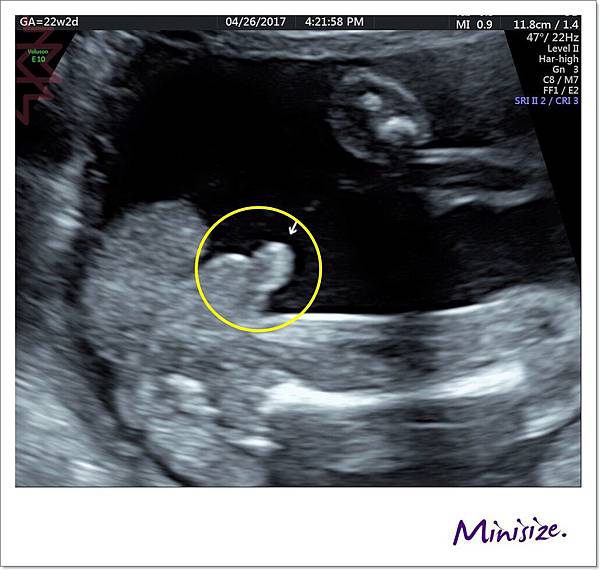

我選取幾張比較有趣的超音波照片解說就好

脊椎

骨骼要呈現排列整齊相互對稱

背部皮膚的表層也要光滑 完整連接

腦

箭頭處為透明中膈要明顯

左右腦也要對稱